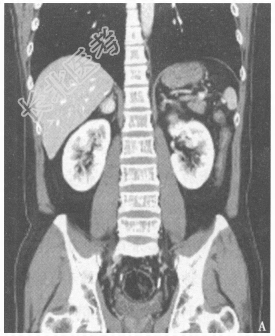

- 简答题3、患者的腹部+盆腔CT检查结果见图4、图5。患者目前可能的诊断是